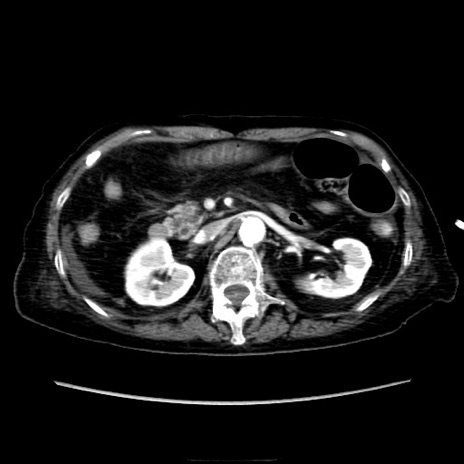

症例40(横断像)

【症例】90歳代女性

【主訴】腹痛・嘔吐

【現病歴】 食欲低下、嘔吐があり昨日他院受診。肺炎と診断され入院となる。入院後より腹部全体に圧痛あり。胃管留置され経過みていたが、症状持続するため、

当院転院となる。

【既往歴】胸椎圧迫骨折、胆石症

【身体所見】腹部:中央に激痛あり、圧痛あり、反跳痛不明

【データ】WBC 17100、CRP 18.82

横断像